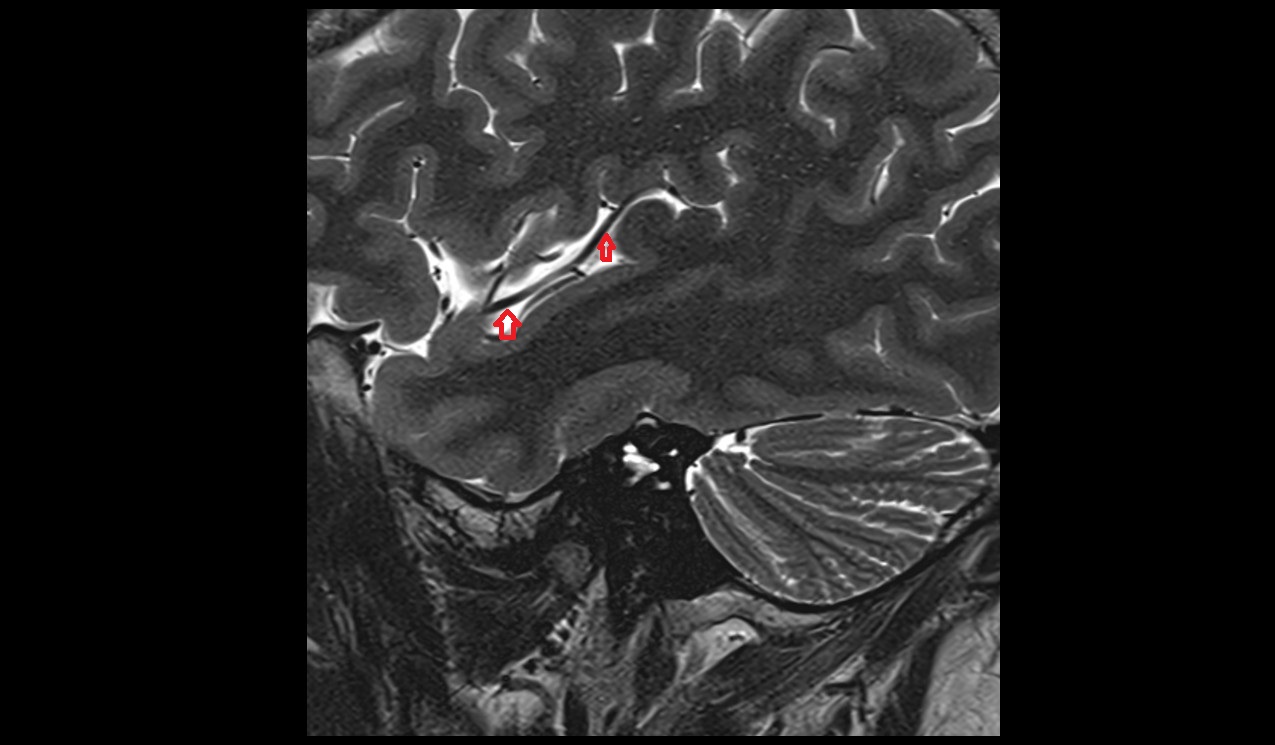

- Lateral sulcus (Sylvian fissure)

- Cistern of central sulcus